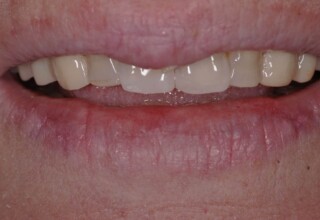

Composite Resin Veneers

Resin veneers are an inexpensive mode of esthetic improvement of anterior teeth, premolars also. Their potential is admirable and their limit is the operator’s clinical dexterity and imagination. In this case there were multiple problems with the upper four incisors: staining, poor inclinations, diastemas, multishading, poor interrelationship and poor tooth-gingiva ratios. They were restored with four direct composite resin veneers (one on a porcelain implant crown!) which were manufactured intraorally!!!